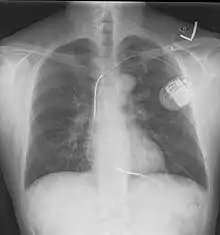

مزيل الرجفان المغروس

بعد النجاة من الرجفان البطيني فإن المرضى الذين عانوا من الرجفان البطيني لأسباب غير رجعية يجب حمايتهم من تكرار الرجفان البطيني عن طريق غرس جهاز مزيل الرجفان المغروس (بالإنجليزية: ICD or implantable cardioverter defibrillator). هذا الجهاز شبيه بناظم الخطى، ويقوم بمراقبة مخطط القلب الكهربائي وتحليله، يقوم الجهاز بتوجيه صدمة كهربية للقلب عن طريق أقطاب مغروسة حول القلب منهياً بذلك الرجفان البطيني.